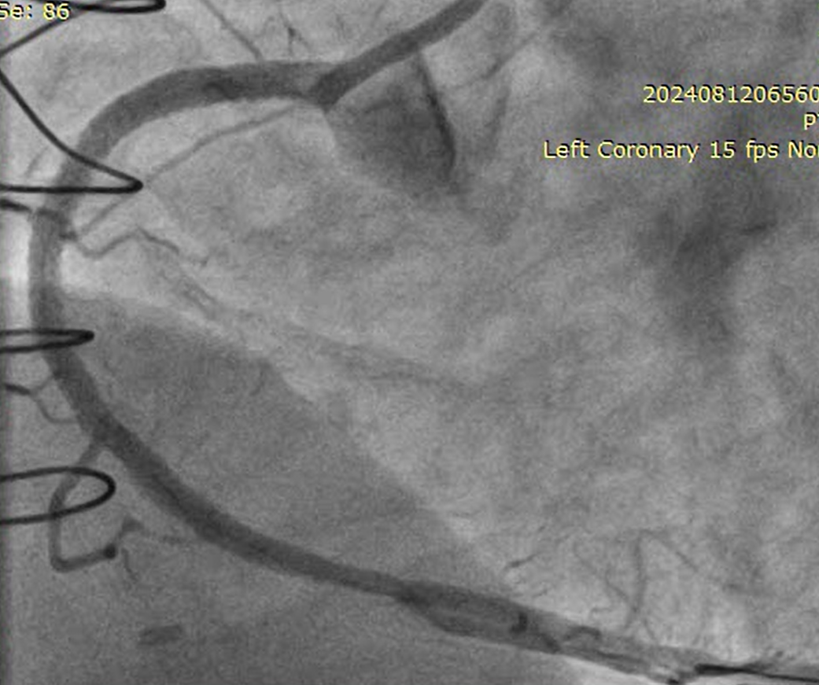

RSVG to Ramus to PLV was engaged with 7F AR-1 guide catheter. Occluded segment in RSVG crossed with Pilot-150 PTCA wire with Caravel micro-catheter and parked into distal RCA. Position of the wire and micro-catheter confirmed with retrograde injection from native LMCA. Retrograde wiring was attempted with Gaia NexT-2, Pilot-150, Pilot-200 PTCA guide wires, but was unsuccessful. Native RCA was engaged with 7F AL 0.75 guide catheter and antegrade wiring was attempted with micro-catheter support and Gaia NexT-2, Pilot-150 followed by Pilot-200 PTCA guide wires, but was unsuccessful. Balloon dilatation was done in proximal RCA with 2.0 x 10 mm SC balloon. Knuckle wire technique was used to cross the lesion from antegrade site but unsuccessful. Finally, lesion crossed with Asahi Gladius MG-14 wire from antegrade approach and wire parked into the RSVG. Micro-catheter exchanged. Serial predilatation was done with 0.75 x 8 mm SC balloon followed by 2.0 x 20 mm SC balloon. IVUS run was taken for vessel size estimation. 3.0 x 48mm DES was deployed from proximal RCA. Post dilatation was done with NC 3.5 x 8 mm balloon. Distal RCA was addressed with 2.75 x 30 mm DEB. Mid RCA was stented with DES 3.00 x 32 mm. Post-dilated with 3.0 x 10 mm NC balloon followed by 3.75 x 8 mm NC balloon. Post-stenting IVUS run showed good stent expansion and apposition. Distal TIMI-III flow was achieved.

Occluded and degenerated venous grafts are better not to be intervened if not acute occlusion. Septal collaterals are best for retrograde CTO intervention but in our case the occluded SVG graft which was sequentially connected to ramus followed by the PLV branch of RCA proved to be a very good channel for the same. Appropriate wire escalations and sequential retrograde CTO techniques need to be carefully used. In our case Retrograde CART technique was successfully used followed by antegrade wire crossing. Ultimately the CTO lesion was treated thereafter antegradely. Intracoronary imaging is essential for such case and IVUS was used in our case.